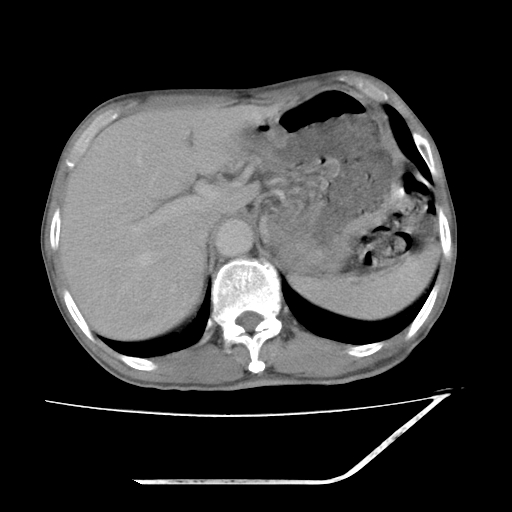

平扫

增强

支持 右侧肾盂癌伴肾静脉瘤栓形成可能性大,右肾结石;肝右叶后段低密度影,不除外转移。

1.右侧肾盂癌伴肾盂积水。

2.肾脏功能减退,原因有:(1)肾动脉受侵。(2)肾静脉受侵(3)肾积水,等。本例,肾动脉显影较好,但受压明显;肾静脉无明显显示,受压或静脉癌栓,下腔静脉腔内未见明显充盈缺损。